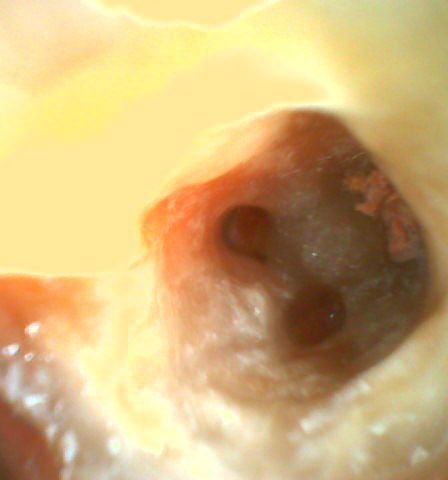

ほぼ近心根のお薬がはずれたと思います。 下図 ↓

このお薬をはずすのはすごく大変です。